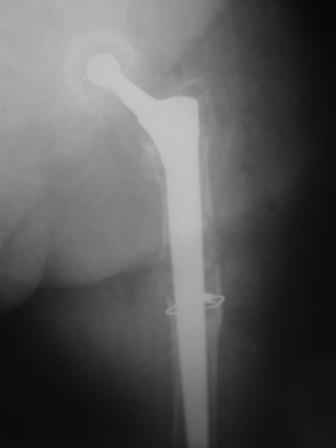

Спасибо за обсуждение. После нескольких дней тракции аппаратом сделали. Попытка закрытой репозиции не удалась из-за смещения по ширине, мешали фрагменты цемента. После их удаления репозиция получилась. Еще убрали немного цемента с ножки по латерльной стороне, чтобы обнажить 40-50 мм ее дистальной части, для плотной посадки гвоздя. Дальнейшее введение гвоздя было несложным. Протез показался нам стабильным в проксимальной части как латерально, так и медиально. Картинки в приложении.

THX for the discussion. After few days of traction by ex-fix the surgery was performed. An attempt of closed nailing was unsuccesful because of fragment translation, which was blocked by cement fragments. After removal of broken cement pieces reduction was reached "automagically". Also some cement from lateral part was removed by

chisel to expose distal 40-50 mm of the stem to allow tight fit of the nail. Further fixation by the nail was pretty easy and straightforward. Images attached. The stem looked stable in its proximal part both laterally and medially. Comments/critics are welcome.